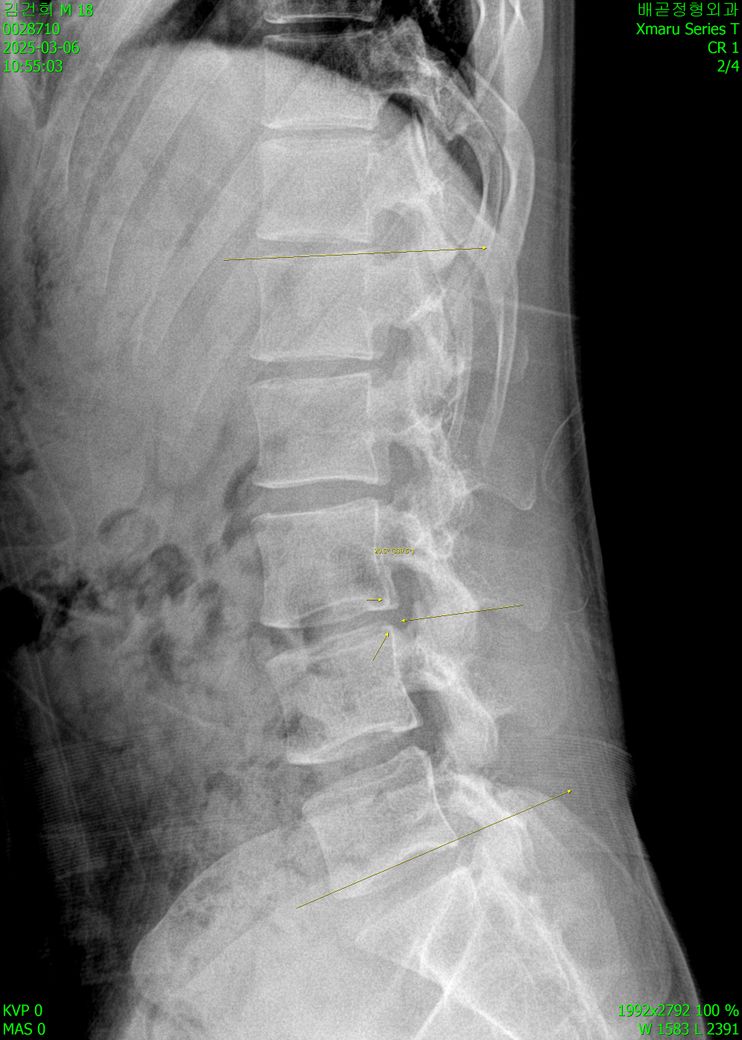

엑스레이 상으로 심하게 휘어져있나요?

문제되는 부분들 전부 지적해주세요 ㅠㅠ

심한 정도도 궁금해요

오늘 진료받고 왔는데 선생님께서

나이에 비해 심하다고 하셔서요 ㅠㅠ

• 2번 째 사진

엑스레이사진을 보니 일단 옆으로 찍은 사진이랑 정면에서 찍은 엑스레이로 확인이 되고 일단 엑스레이상 척추 뼈의 정렬은 크게 틀어지거나 하지는 않은 것으로 보이나 옆으로 보았을때 허리뼈의 만곡이 약간 감소 되어있기는 하지만 통증이 없다면 크게 걱정하실 필요는 없을 것으로 생각되며 평소 자세와 습관등을 고쳐주시고 적절한 운동을 통해 허리의 만곡을 잘 만들어 주시면 좋을 것 같습니다.

좌우 대칭이 맞지않고, 척추의 곡선이 일자에 가까워지는 것으로 보입니다.

사진상으로 많은걸확인할수없지만 약간의 허리측만과 허리커브의감소가보입니다 이럴경우 허리쪽으로 지속적으로 부담이나 스트레스가 생길수있기때문에 허리의 커브를만들어주는동작이나 중립척추를 유지하면서 할수있는 코어운동을 평소에 꾸준하게하는것이 도움이될수있습니다